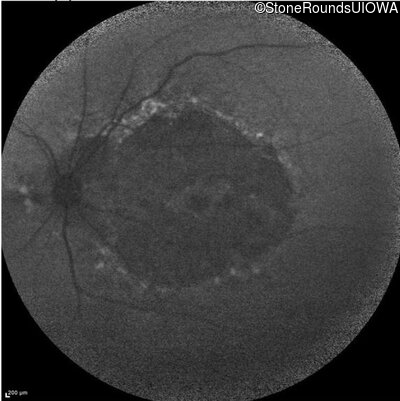

Age at visit: 59 years

This 59 year old woman first experienced defects in her mid peripheral field in the past year. Her hearing worsened in her 30's and she started wearing hearing aids at age 40. She was diagnosed with diabetes at age 39 and began using insulin at age 42.